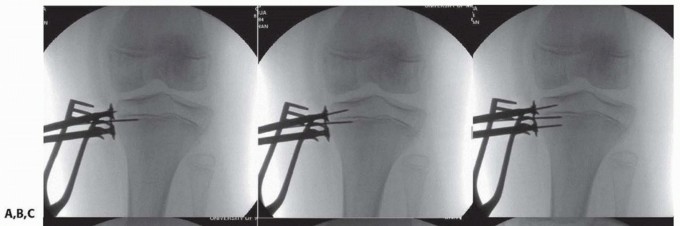

-

- ### TECH FIG 1 • A. A guide pin has been placed into the physis and the plate slid over the guide pin to properly center it. B. An epiphyseal pin is placed parallel or slightly divergent to the physis. C. A metaphyseal pin is placed second aiming parallel or slightly divergent to the physis. D,E. The near cortex was drilled and then fully threaded cannulated screws were placed over the guide pins. F. Lateral fluoroscopic image of the proximal tibia demonstrating the midsagittal positioning of the plate.

- ### Guide pins are then inserted through the plate in a parallel to slightly divergent fashion from the physis, placing the epiphyseal pin first, followed by the metaphyseal pin. Confirm proper position with fluoroscopy and avoid inadvertent physeal or joint disruption (TECH FIG 1B,C).

- ### The near cortex is drilled and then a fully threaded screw is inserted (cannulated or solid screws depending on surgeon preference) (TECH FIG 1D,E).

- ### Confirm final screw positions with fluoroscopy (TECH FIG 1E,F).